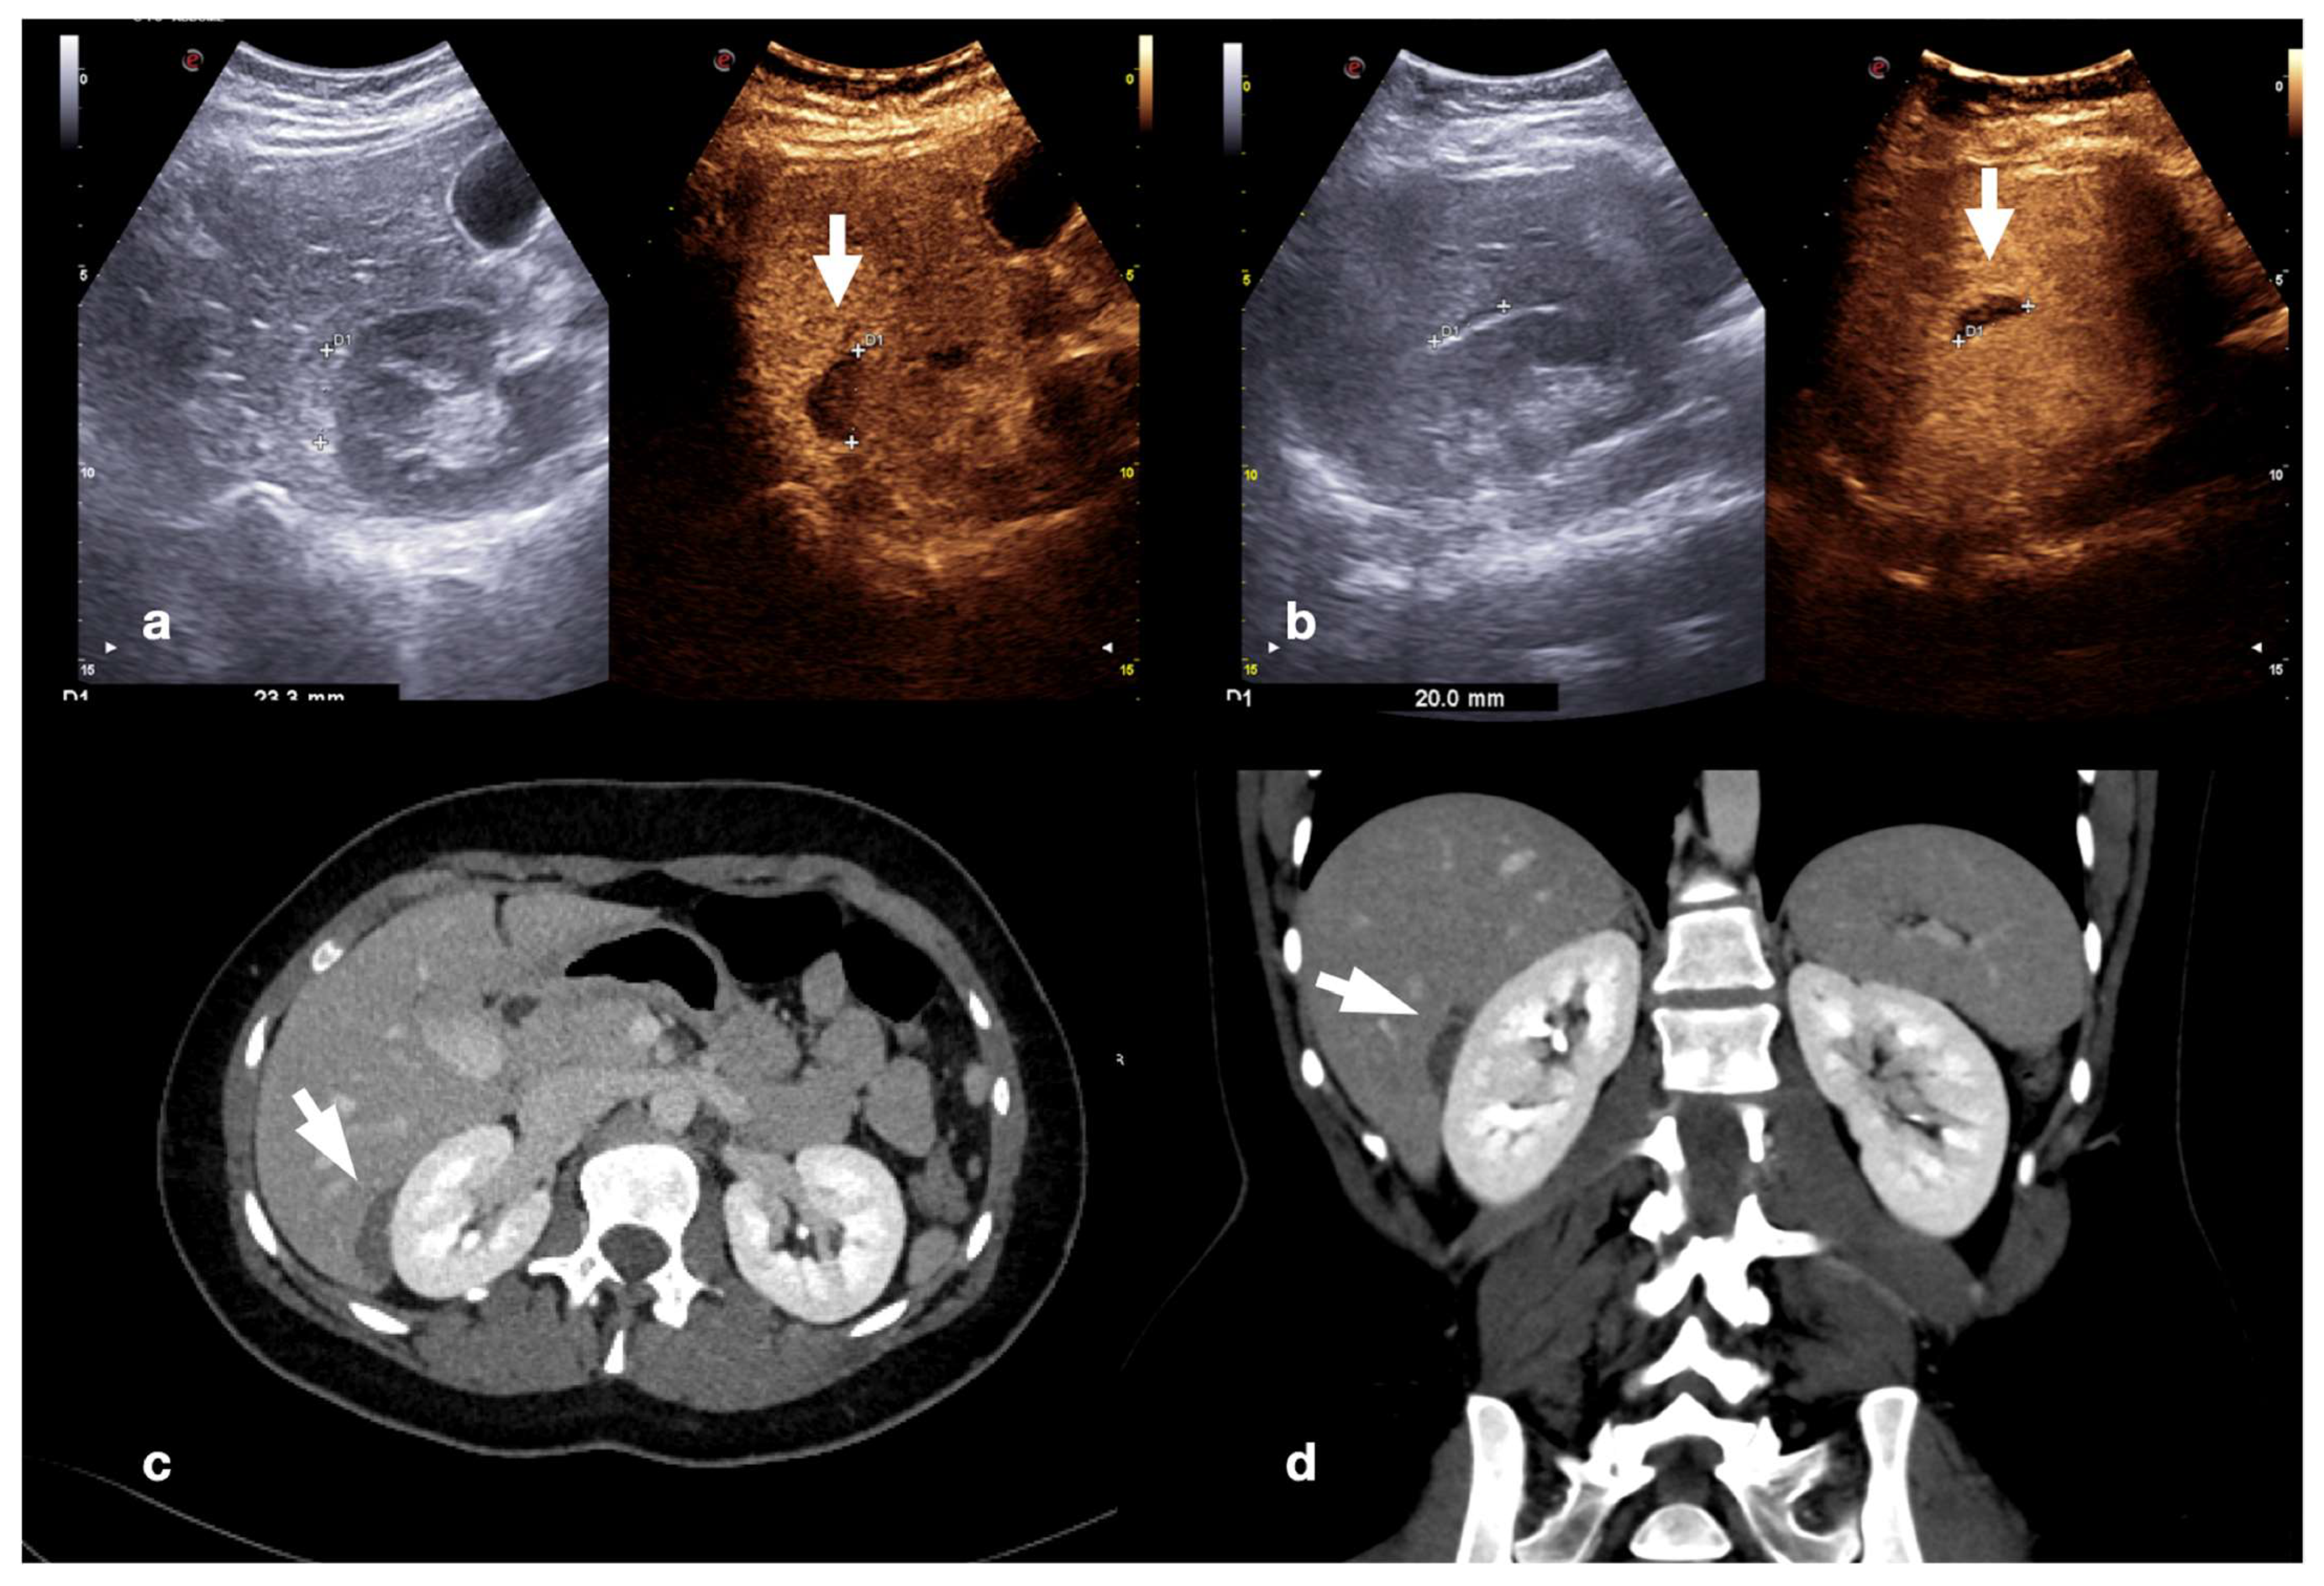

2.3.1. Solid Organ Injuries May Involve the Parenchyma and the Vessel

- Parenchymal injuries:

4. Case Series: Step-by-Step Practical Applications, Tips and Tricks during CEUS Follow-Up of Conservatively Managed Abdominal Trauma

4.1. Step 1

4.2. Step 2

4.3. Step 3

4.4. Step 4

4.5. Step 5